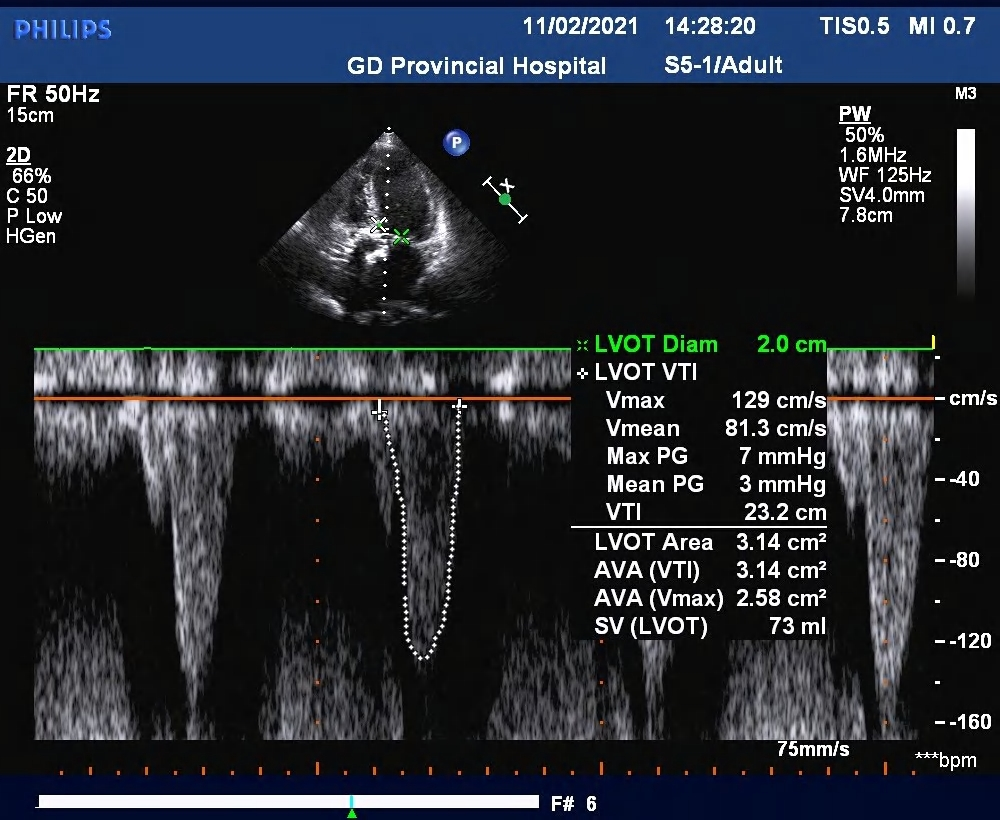

术后超声

主动脉瓣流速 2.98